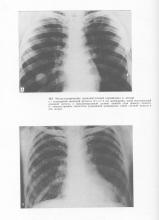

Adenokistoznoy metasztatikus karcinóma regionális nyirokcsomók a nyak csak 8-9%. Az az elképzelés, hogy az áttétek a nyakon, amikor tsilindromah nem fejlődik, nem igazolódott. A tsilindromy jellemző hematogén metasztázis, amely megfigyelhető a 40-45%. Gyakran alakulnak ki áttétek a tüdőben és a csontok (ábra. 163-164), és néha úgy tűnik, nagyon korán, és vezet a tömeges elpusztítása.